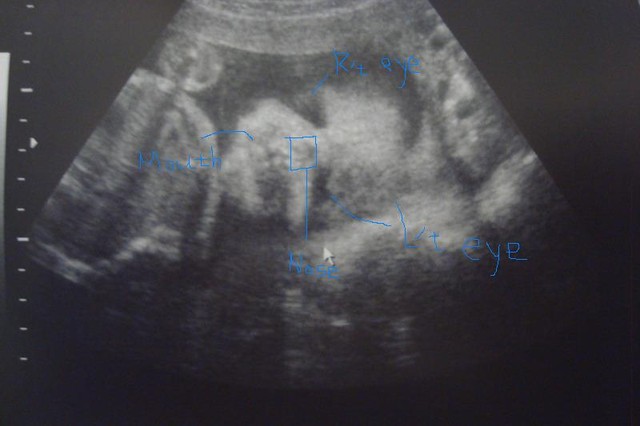

不專業圖解如下:

希望對您了解寶寶的超音波有那麼一點點微小的幫助......